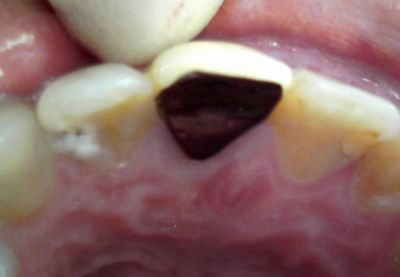

■女性:前歯がしみる

右上2番、口蓋側遠心に齲蝕。

これが深い齲蝕で、

軟化象牙質除去中に露髄。

これは止血できたので、MTAで直覆し、

CRで充填。

術後に若干冷水痛が残ったが、予後は現在のところ良好である。